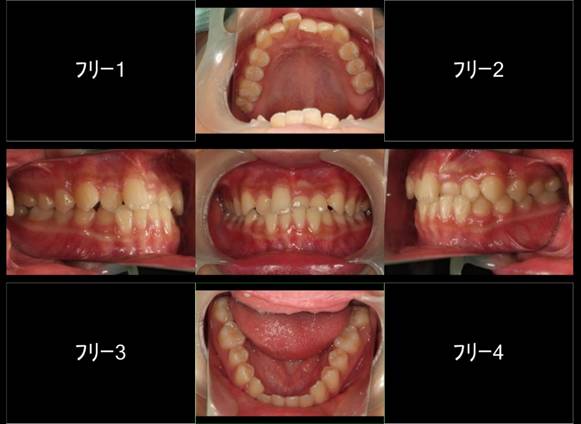

上顎前突+叢生 抜歯矯正(治療期間1年)

治療前、特に上の歯並びに問題がありました

奥歯のかみ合わせもよくありません

口元が突出しています

治療後、正中線も揃いました

小臼歯を抜歯しました

きちんと噛んでいます

大変きれいな横顔になりました。もともと明眸でしたので、矯正治療で明眸皓歯になりました。

笑顔もチャーミング